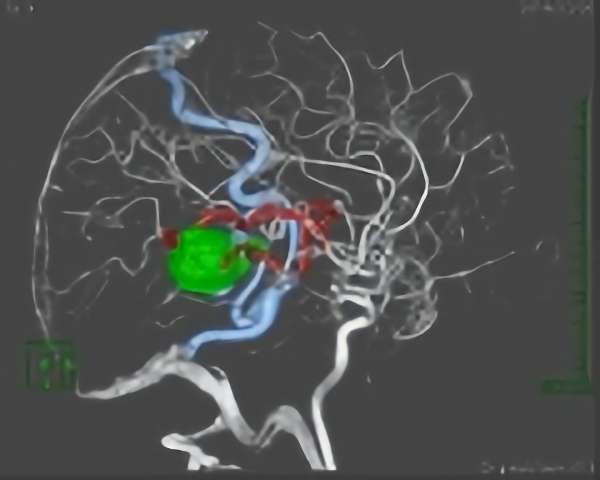

Cerebral Arteriovenous Malformation

脳動静脈奇形(AVM)治療センター

治療センターについて